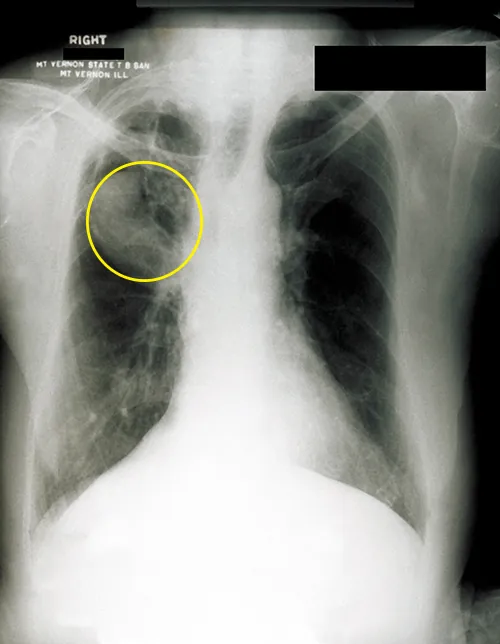

An X ray showing white bones on a black background. White webbing in the upper lung is circled.

Figure 22.26 A fungal ball can be observed in the upper lobe of the right lung in this chest radiograph of a patient with aspergilloma. (credit: modification of work by Centers for Disease Control and Prevention)